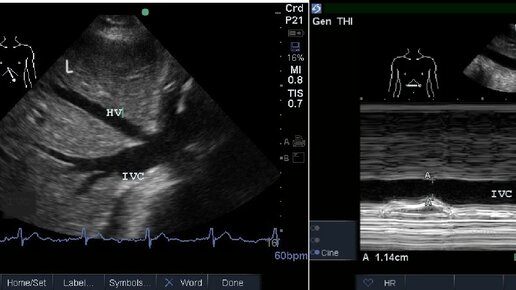

Ультразвуковые критерии венозного застоя

Острое повреждение почек и другие виды органной дисфункции на фоне сердечной недостаточности в первую очередь определяются низким сердечным выбросом и венозным застоем. Это является следствием повышенного давления наполнения сердца. Ранняя ультразвуковая оценка нижней полой вены у постели больного, УЗИ легких для выявления легочного застоя и эхокардиография все чаще используются для оценки застойной сердечной недостаточности и функции левого желудочка у постели больного. Застой нарушает венозный отток от органов брюшной полости (прежде всего почек и печени)...